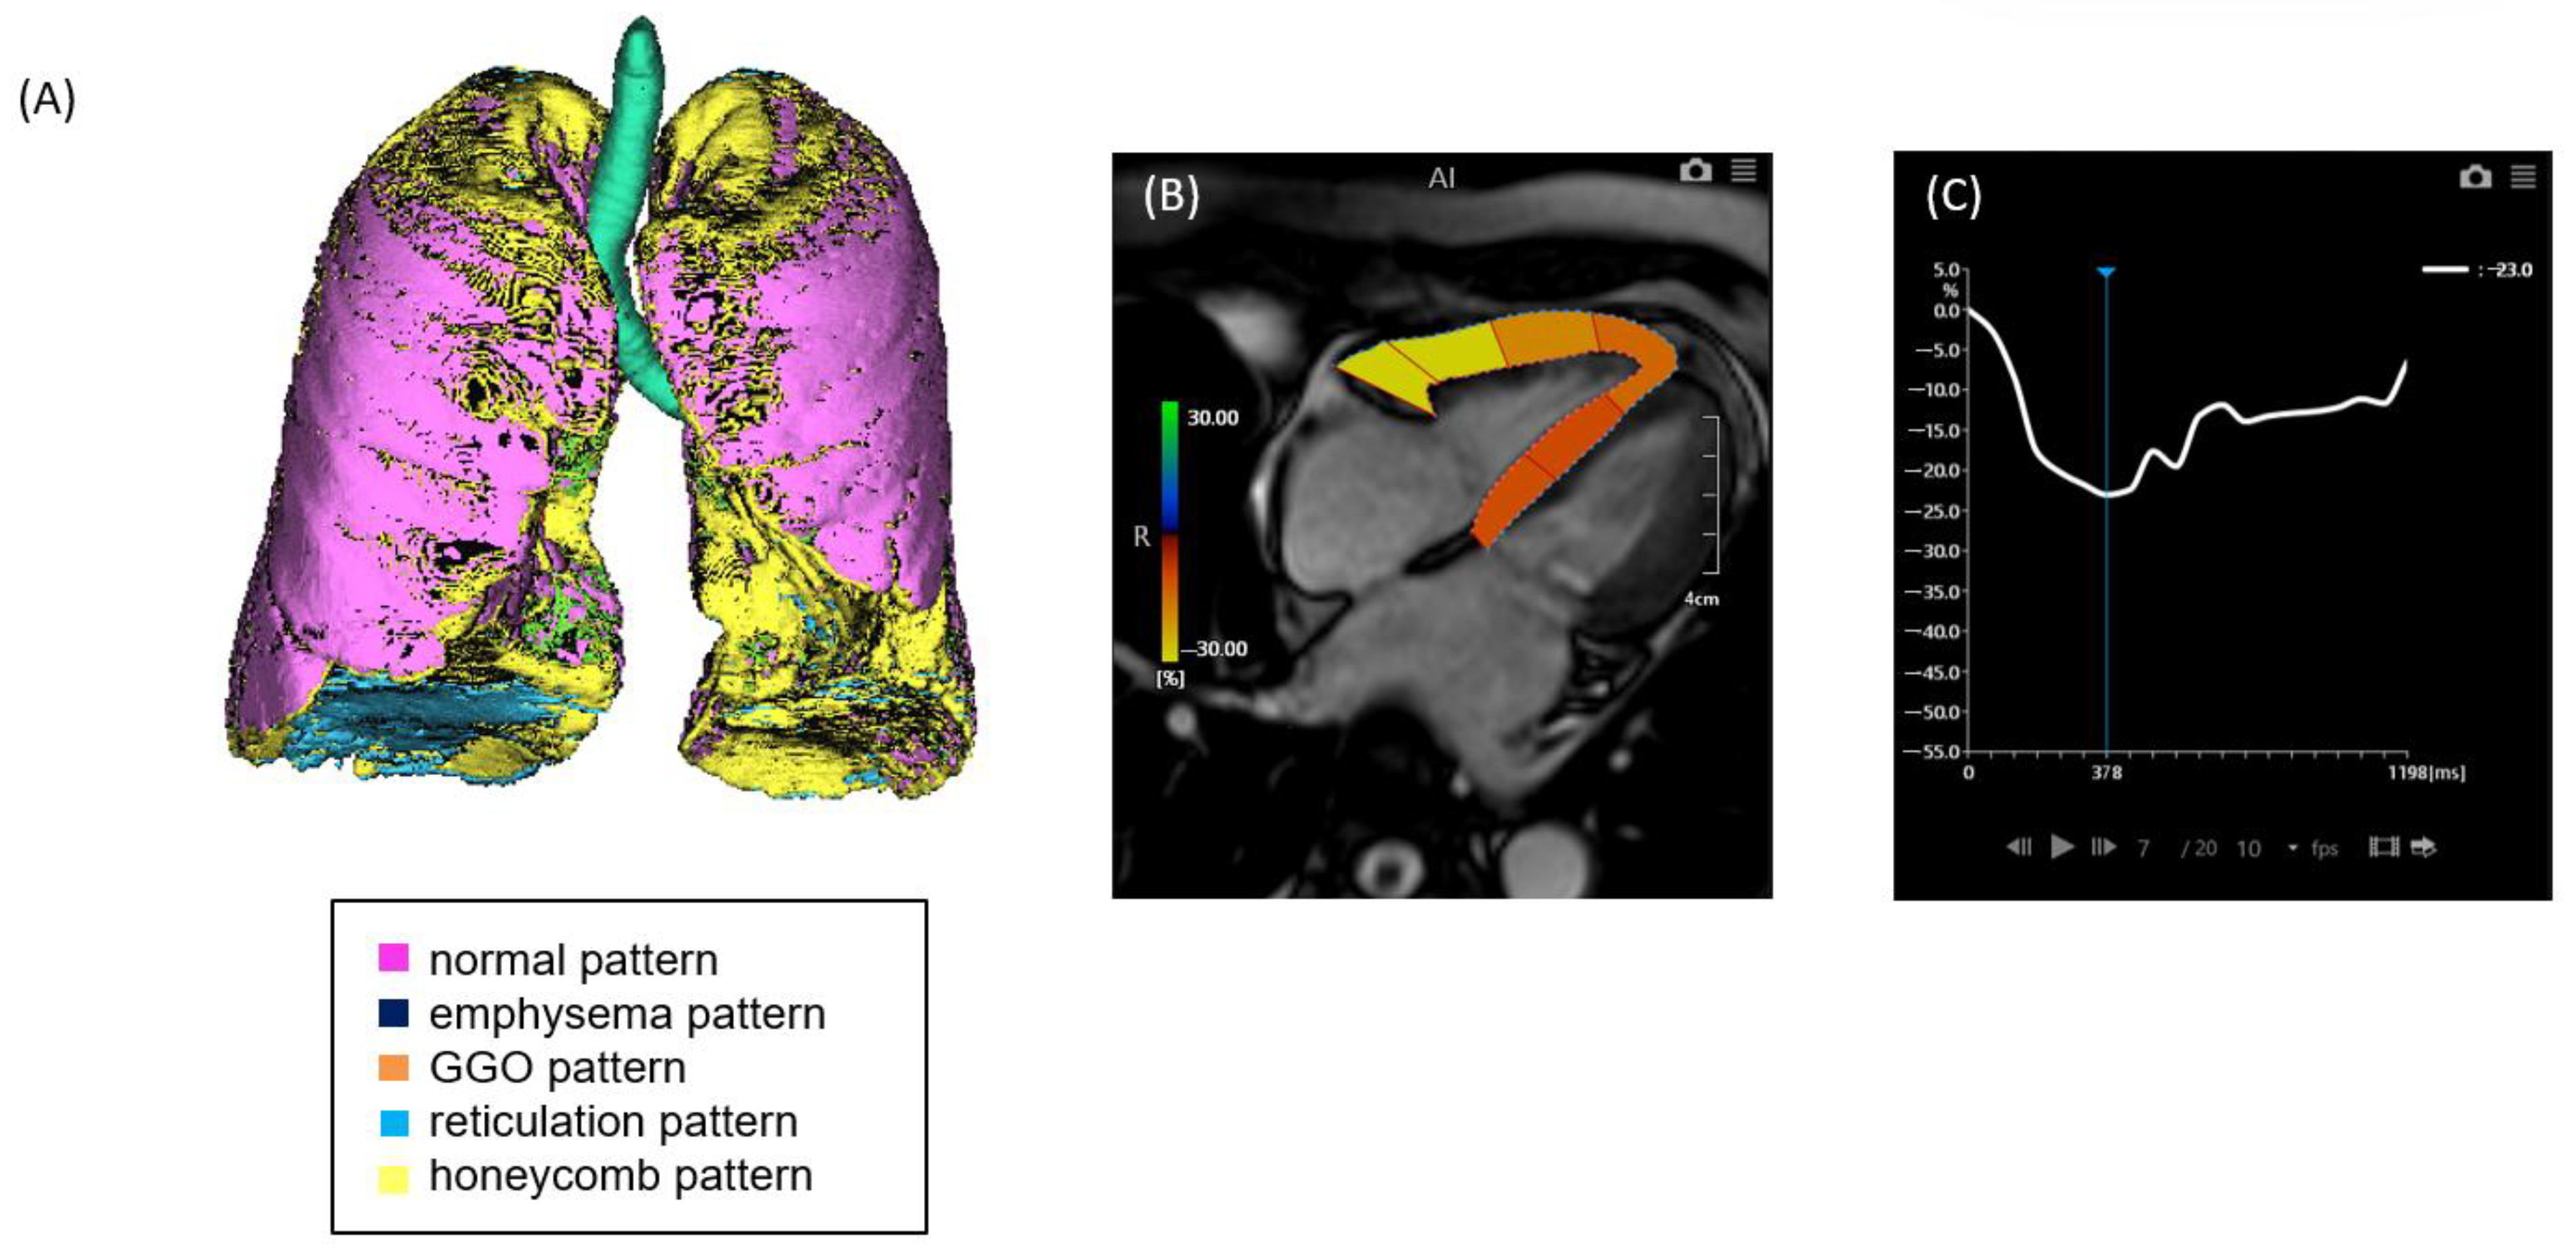

2.2. CT Image Acquisition and Analysis

2.3. MRI Image Acquisition and Analysis